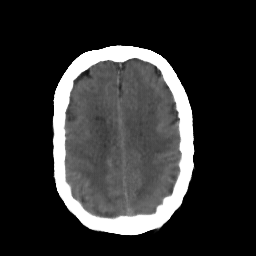

In this study, the dataset introduced in [8], which is publicly available111https://github.com/ChengBinJin/MRI-to-CT-DCNN-TensorFlow, is used for performance evaluation. It consists of 367 paired CT and MR images with the size of 512256. In the original dataset, it is noted that several CT images have stereotactic head frame that was used in Gamma Knife treatment. This head frame manually removed from the CT images. In addition, there exist various CT and MR slices that brings incredible difficulty in training the generator. Therefore, 100 images are selected from similar slices for each modality, in which 90 and 10 images are used for training and testing, respectively. Fig. 5 shows four examples of pre-processed samples.